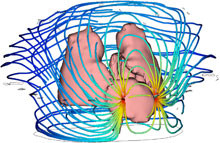

For medical diagnostic purposes there is an increasing need for non- (or minimal) invasive techniques to measure all kinds of parameters that can provide insight in the functioning of cells, organs or organ systems. Currently, Impedance Cardiography (ICG) is used for measurements of the ... 詳細を見る